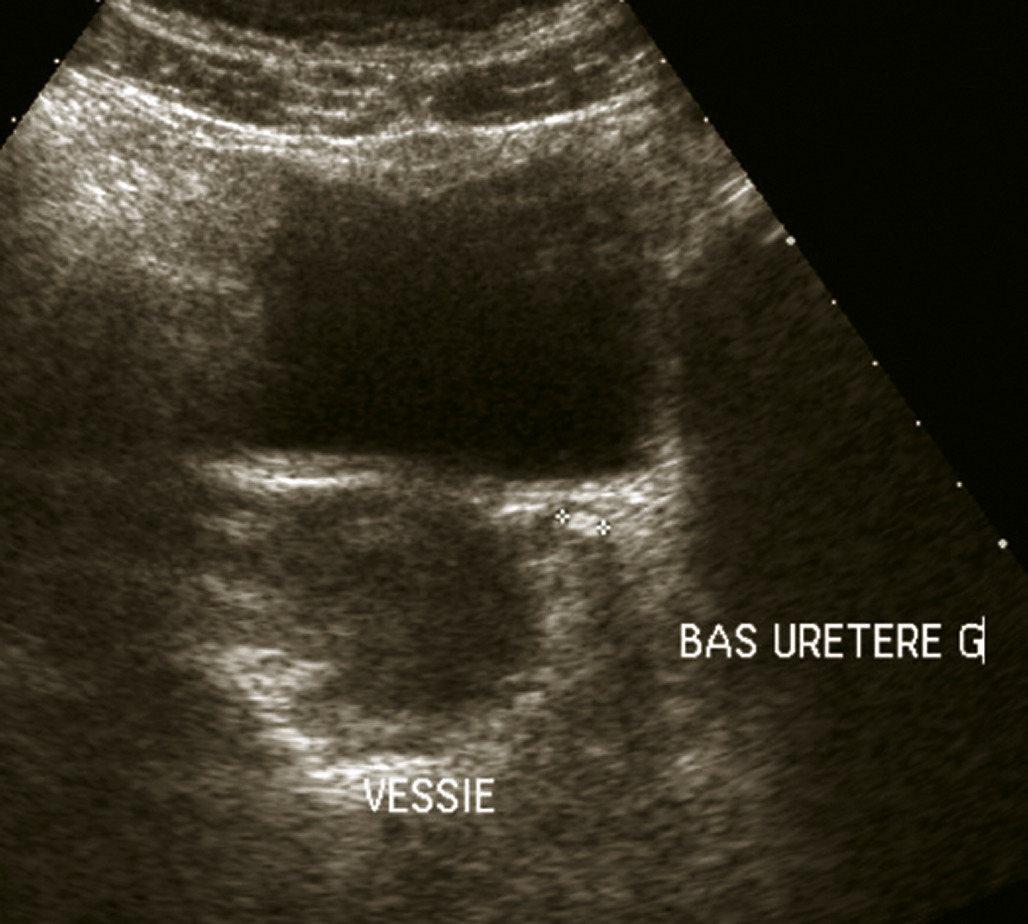

L’échographie abdominale a l’inconvénient d’être opérateur-­dépendante. Ses principales indications sont la lithiase biliaire et ses complications, des douleurs abdominales chez les patients minces et surtout chez la femme pour rechercher une pathologie gynécologique en utilisant le cas échéant des sondes endocavitaires. Ainsi, l’échographie est utile pour affirmer la lithiase biliaire et la cholécystite aiguë (fig. 1) ou objectiver une dilatation de la voie biliaire principale (VBP), rechercher une urétéro-hydronéphrose et des signes indirects en cas de colique néphrétique (fig. 2 et 3), débrouiller le diagnostic des douleurs abdomino-­pelviennes chez la femme.

L’échographie peut montrer une discrète asymétrie des cavités excrétrices rénales, voire l’obstacle lithiasique avec dilatation d’amont (fig. 2 et 3). L’uroscanner complète le bilan et localise si besoin le calcul. Outre le traitement de la cause (calcul, compression extrinsèque…), le traitement antalgique est primordial : anti-inflammatoires non stéroïdiens (AINS), paracétamol, anti­spasmodiques voire dérivés morphiniques. On procédera à la pose d’une sonde urétérale en cas d’anurie (rein unique), de fièvre sur rétention du haut appareil ou de crise hyperalgique.